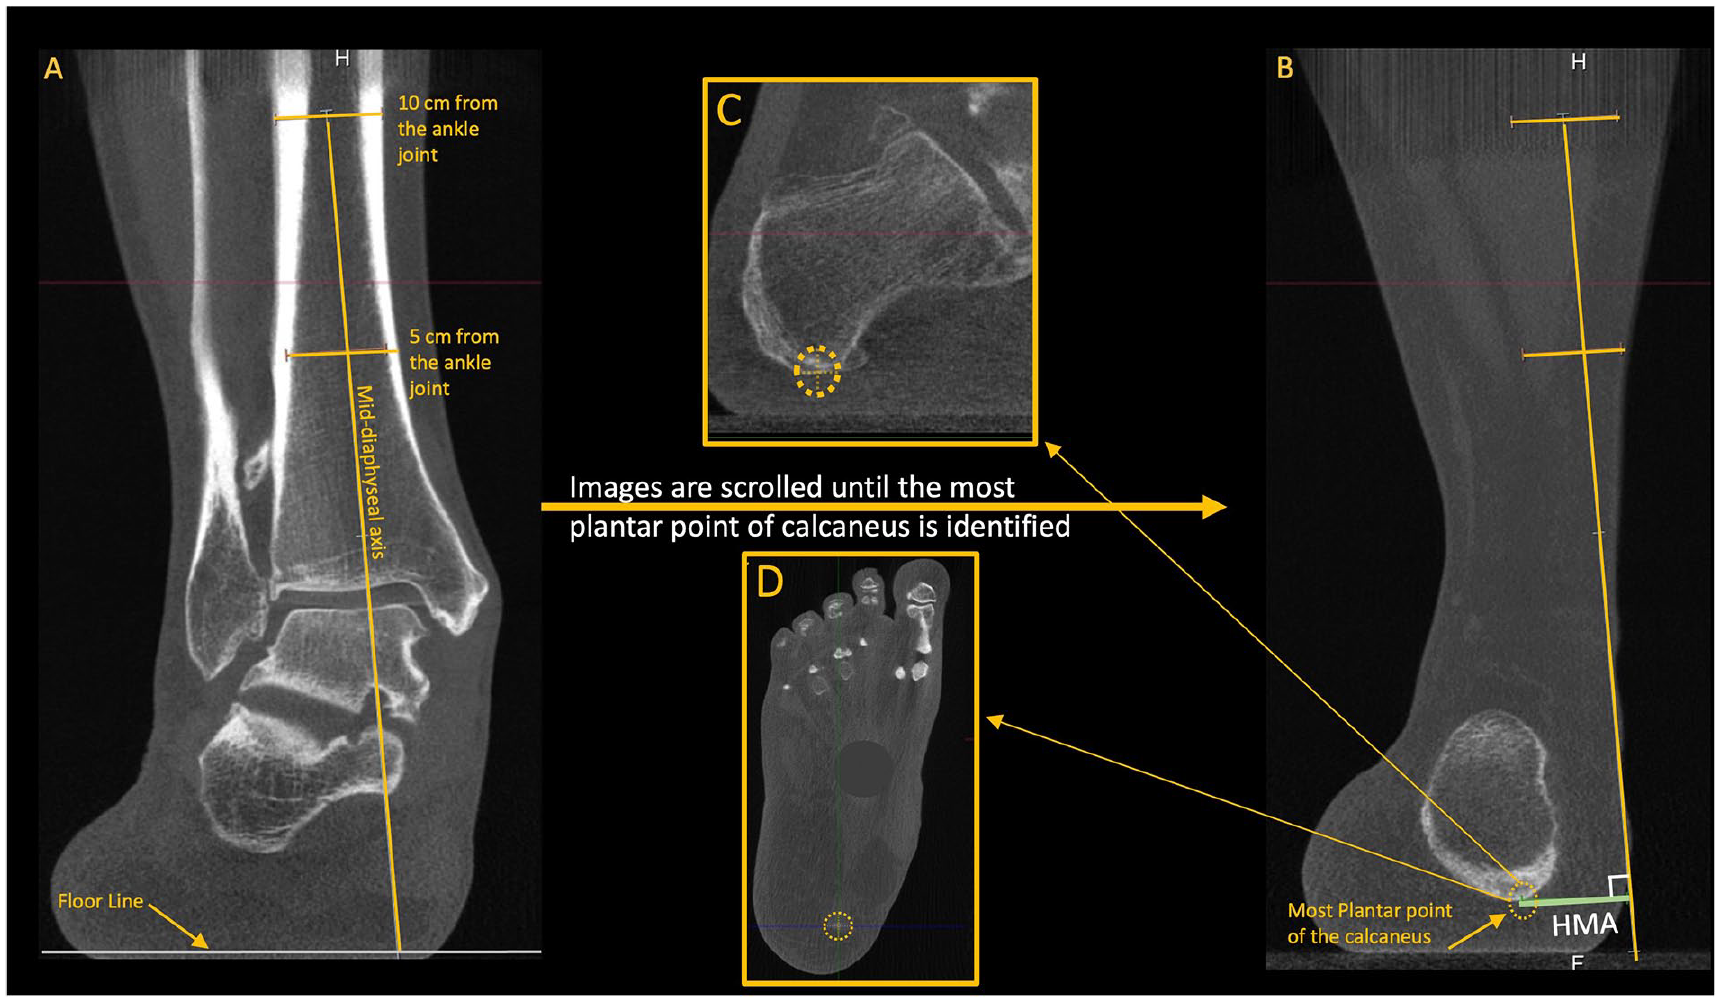

Hindfoot moment arm (HMA). (A) Using the coronal plane, 2 mid-diaphyseal lines are drawn at 5 and 10 cm proximal to the ankle joint to determine the anatomical axis of the tibia. (B) The axis line is then extended inferiorly, crossing the floor line. (B, C, and D) The HMA is determined by the distance between the anatomical tibial line and the most inferior voxel of the calcaneus (confirmed on all planes). 36